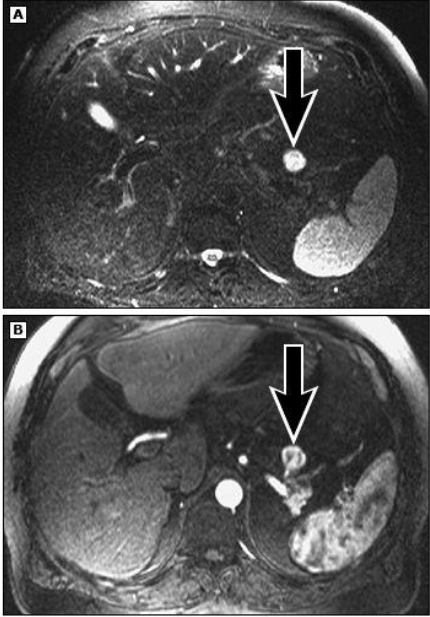

Q

מהו הממצא

A

IPMN

הרחבה של צינור הלבלב יחד עם ציסטה, מדובר בציסטה גידולית

How well did you know this?